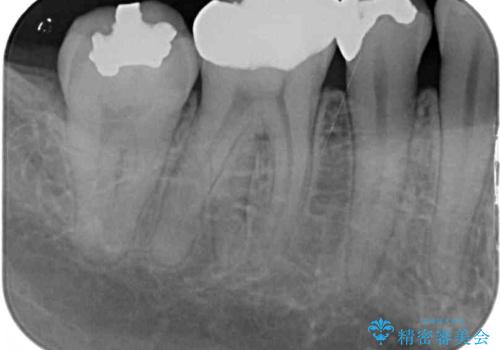

通常の咬み合わせ位置と比較して、上顎の歯列が全体的に前方にある状態で、上下前歯の前後方向の位置に著しい差がありました。

上顎奥歯付近にアンカースクリューを用い、上顎歯列全体の後方移動と、大臼歯圧下を促し、前歯の上下関係を改善することとしました。

奥歯には目立つ銀歯が多くあるので、矯正治療後には下顎の銀歯をセラミッククラウンやセラミックインレーにより、補綴・修復治療することとしました。